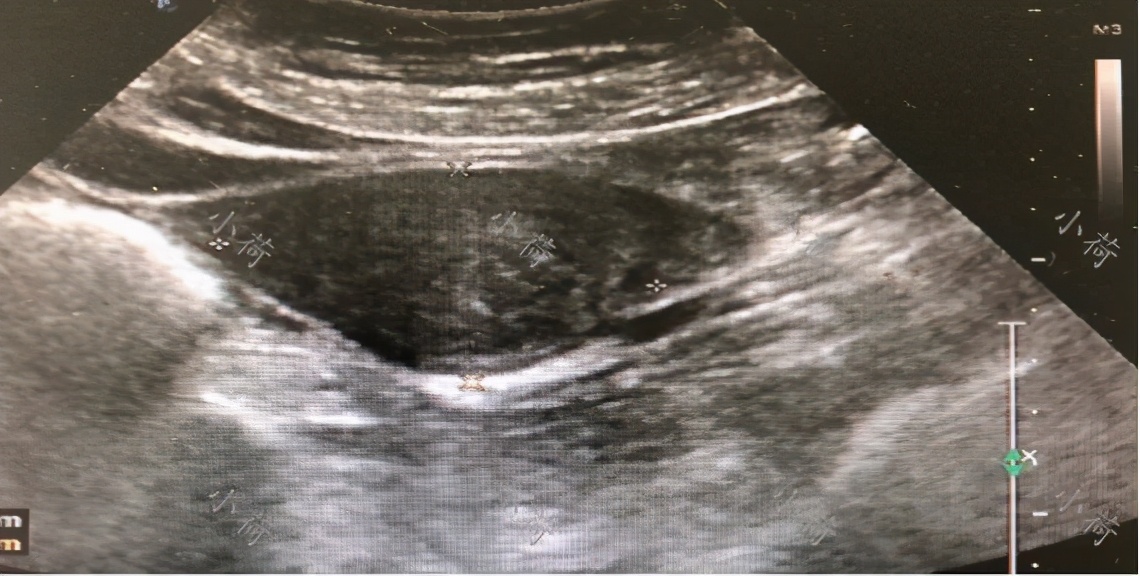

来我院进一步检查发现宫颈上唇一赘生物占据整个宫颈上唇,触之容易出血,当时妇科B超提示:盆腔积液,子宫及双侧附件未见明显异常(图1)。今日未行进一步检查而入院。病人自发病以来,一般情况好,饮食、睡眠好,二便正常。

图1 超声见盆腔积液

妇科超声示子宫前位,大小约56mm×43mm,内部回声均匀,内膜厚约8mm,直肠窝可见范围约29mm×52mm×24mm液性暗区。提示:盆腔积液、子宫及双侧附件未见明显异常。